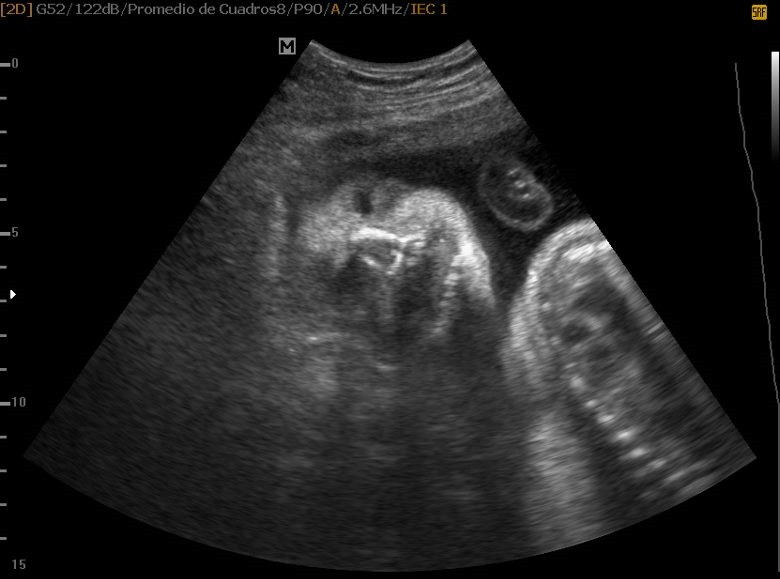

Varias ultrasonografías en 2D y 3D

Envíado por Dr. Nelson Menjívar Sarco